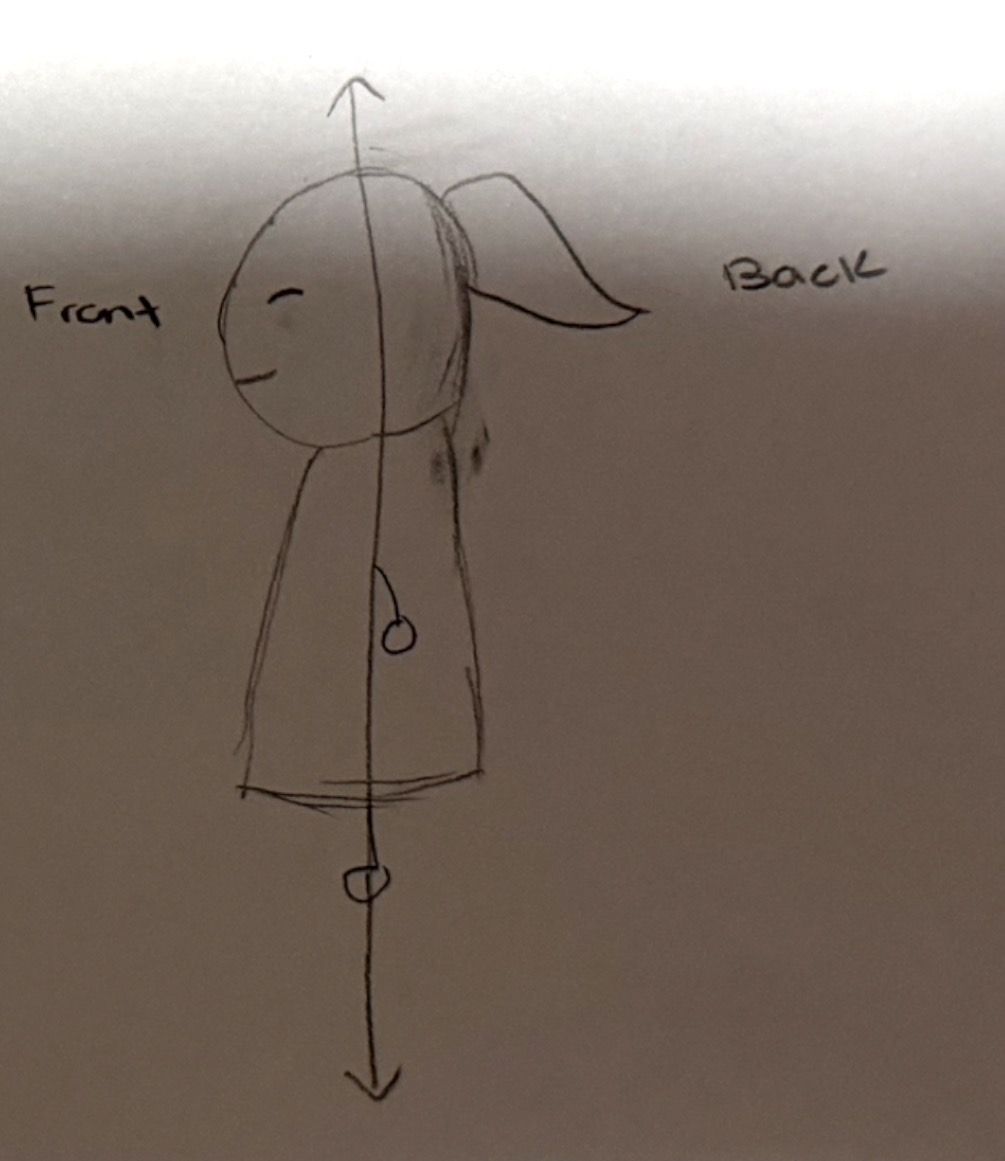

Frontal section

horizontal cut to split body into a front and back section

Anterior

front of body

Posterior

back of body